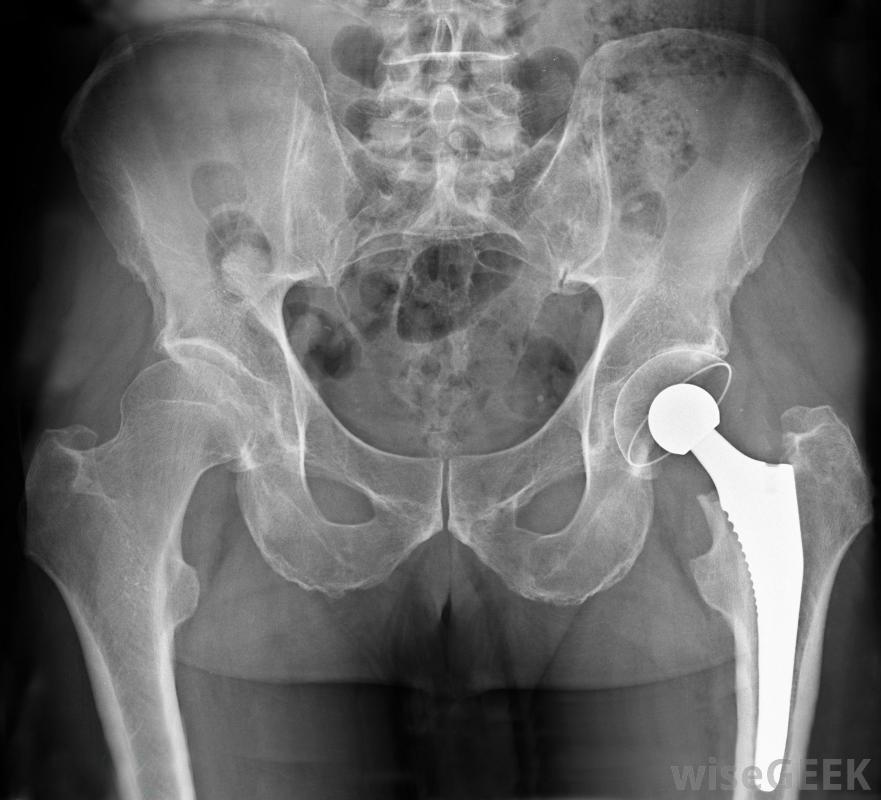

髋关节撞击,也称为股骨髋臼撞击,或FAI,发生在移动髋关节时引起过多的摩擦或摩擦。这通常会导致腹股沟疼痛和关节活动困难,有时会导致关节炎。这些症状在疾病的早期阶段通常不明显,所以FAI通常多年未被诊断,当它出现时,它可能被分为两种形式:凸轮和钳子。这种撞击可能是先天性的,或是在出生时出现的,也可能是随着时间的推移而发展的,通常是由于遗传倾向和环境的综合作用髋关节撞击严重时可采用髋关节置换术治疗股骨和髋臼。股骨是从膝盖到臀部的大骨头,髋臼是骨盆向内弯曲的一部分。股骨的球形端与髋臼的窝状形状相吻合,使腿能够旋转运动。在健康的关节中,骨骼在在股骨和骨盆之间起缓冲作用的滑膜液和软骨。但是,如果其中一块骨头变形,就会引起摩擦、软骨破坏和疼痛MRI扫描可用于诊断股骨髋臼撞击当股骨头的形状不正确时,通常是由于骨头上的损伤而造成的。这可能会导致向前运动时的不适,例如当把膝盖放在胸前或骑自行车时。这种情况会导致髋臼受到不正常的力,并磨损髋臼软骨。凸轮-髋部撞击可因先天或发育原因而发生。创伤可导致骨骼畸形,或患者可能患有髋内翻、股骨头骨骺滑脱(SCFE)或缺血性坏死(AVN)。

酒精中毒可能导致缺血性坏死。a医生可以使用多种方法来诊断FAI。医生会查看患者的病史,倾听症状,进行身体检查,并通常进行X光检查。还可以要求MRI(磁共振成像)排除其他导致僵硬和疼痛的原因。如果患者被诊断为髋关节撞击,医生可能会尝试手术矫正关节的形状和方向。但是,如果软骨损伤严重,髋关节置换术可能是最好的选择。